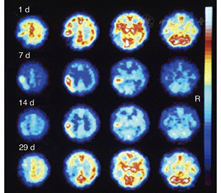

1.脑缺血病灶的检测。SPECT脑灌注显像及PET的血流和代谢研究[27,28]可探查缺血部位及缺血病灶的范围,这2种技术在检测梗死发生时间和梗死范围方面均比CT更为灵敏。在脑卒中发生后的第1个8小时,SPECT检测结果阳性率为90%,灵敏度为61%~74%,特异性为88%~98%[29]。早期PET研究显示,局部缺血部位存在血流和葡萄糖摄取差异,表明存在无氧糖酵解[30],测定氧摄取分数(oxygen extraction fraction, OEF)可使研究人员在梗死发生后的48 h内继续监测梗死的进展情况[31]。在此期间,增加灌注可观察到组织的不可逆损害,称为过度灌注[32];后期在梗死灶中心及周边区域可观察到相对充血(图1)。短暂性脑缺血发作可区别于缺血性卒中而发生在出现症状后的6 h内,SPECT在病侧的计数率为对侧的70%(脑卒中组织灌注值为对侧的35%~60%)[33];PET在病灶部位的CBF显著降低,但OEF增加[34]。

脑卒中早期,PET研究[40,41,42,43]发现脑缺血区域由不同的组织构成。测量时(通常在脑卒中发生后的几个小时)rCBF低于12 ml·100 g-1·min-1的组织或CMRO2低于65 mmol·100 g-1·min-1的局部区域在后期CT扫描中被发现是梗死区域。缺血区域残存的CMRO2是神经元相对完整的一个指标,预示该区域CBF将减少至12~22 ml·100 g-1·min-1。这种不完全的缺血灌注模式[41]是一个缺血半暗带,该区域的OEF增加(由正常值40%上升到80%)。PET研究将缺血区域分为3个部分:缺血核心区(12 ml·100 g-1·min-1),通常呈现出坏死;缺血半暗带区(12~22 ml·100 g-1·min-1),是仍然存活的组织,但可能发生梗死,也可能恢复功能;低灌注区(22 ml·100 g-1·min-1),没有受到血液供应不足的明显损害(图2)。缺血半暗带的进展及转化为梗死是一个动态过程,不可逆损伤的发生也是从缺血中心向周边进展。PET可对这个病理进展过程进行跟踪,并对动物模型和急性脑卒中患者的生理变量进行研究[44,45,46](图2)。